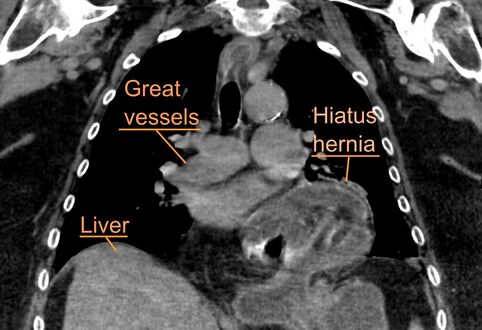

يتم تشخيص فتق الحجاب الحاجز عادةً من خلال سلسلة تصوير الجهاز الهضمي العلوي، التنظير الداخلي، قياس الضغط عالي الدقة، مراقبة درجة حموضة المريء، والتصوير المقطعي المحوسب. يسمح ابتلاع الباريوم كما في سلسلة تصوير الجهاز الهضمي العلوي لرؤية حجم المريء وموقعه وتضيقه. كما يمكنه تقييم حركات المريء. يمكن للتنظير الداخلي تحليل السطح الداخلي للمريء بحثاً عن التآكلات والقرح والأورام.

وفي الوقت نفسه، يمكن لقياس الضغط تحديد سلامة حركات المريء ووجود ارتخاء المريء. وتسمح اختبارات الأس الهيدروجيني بالتحليل الكمي لنوبات الارتجاع الحمضي. كما أن التصوير المقطعي المحوسب مفيد في تشخيص مضاعفات الفتق الحجابي مثل الالتواء المعدي، واسترواح الصفاق، واسترواح المنصف.[8]